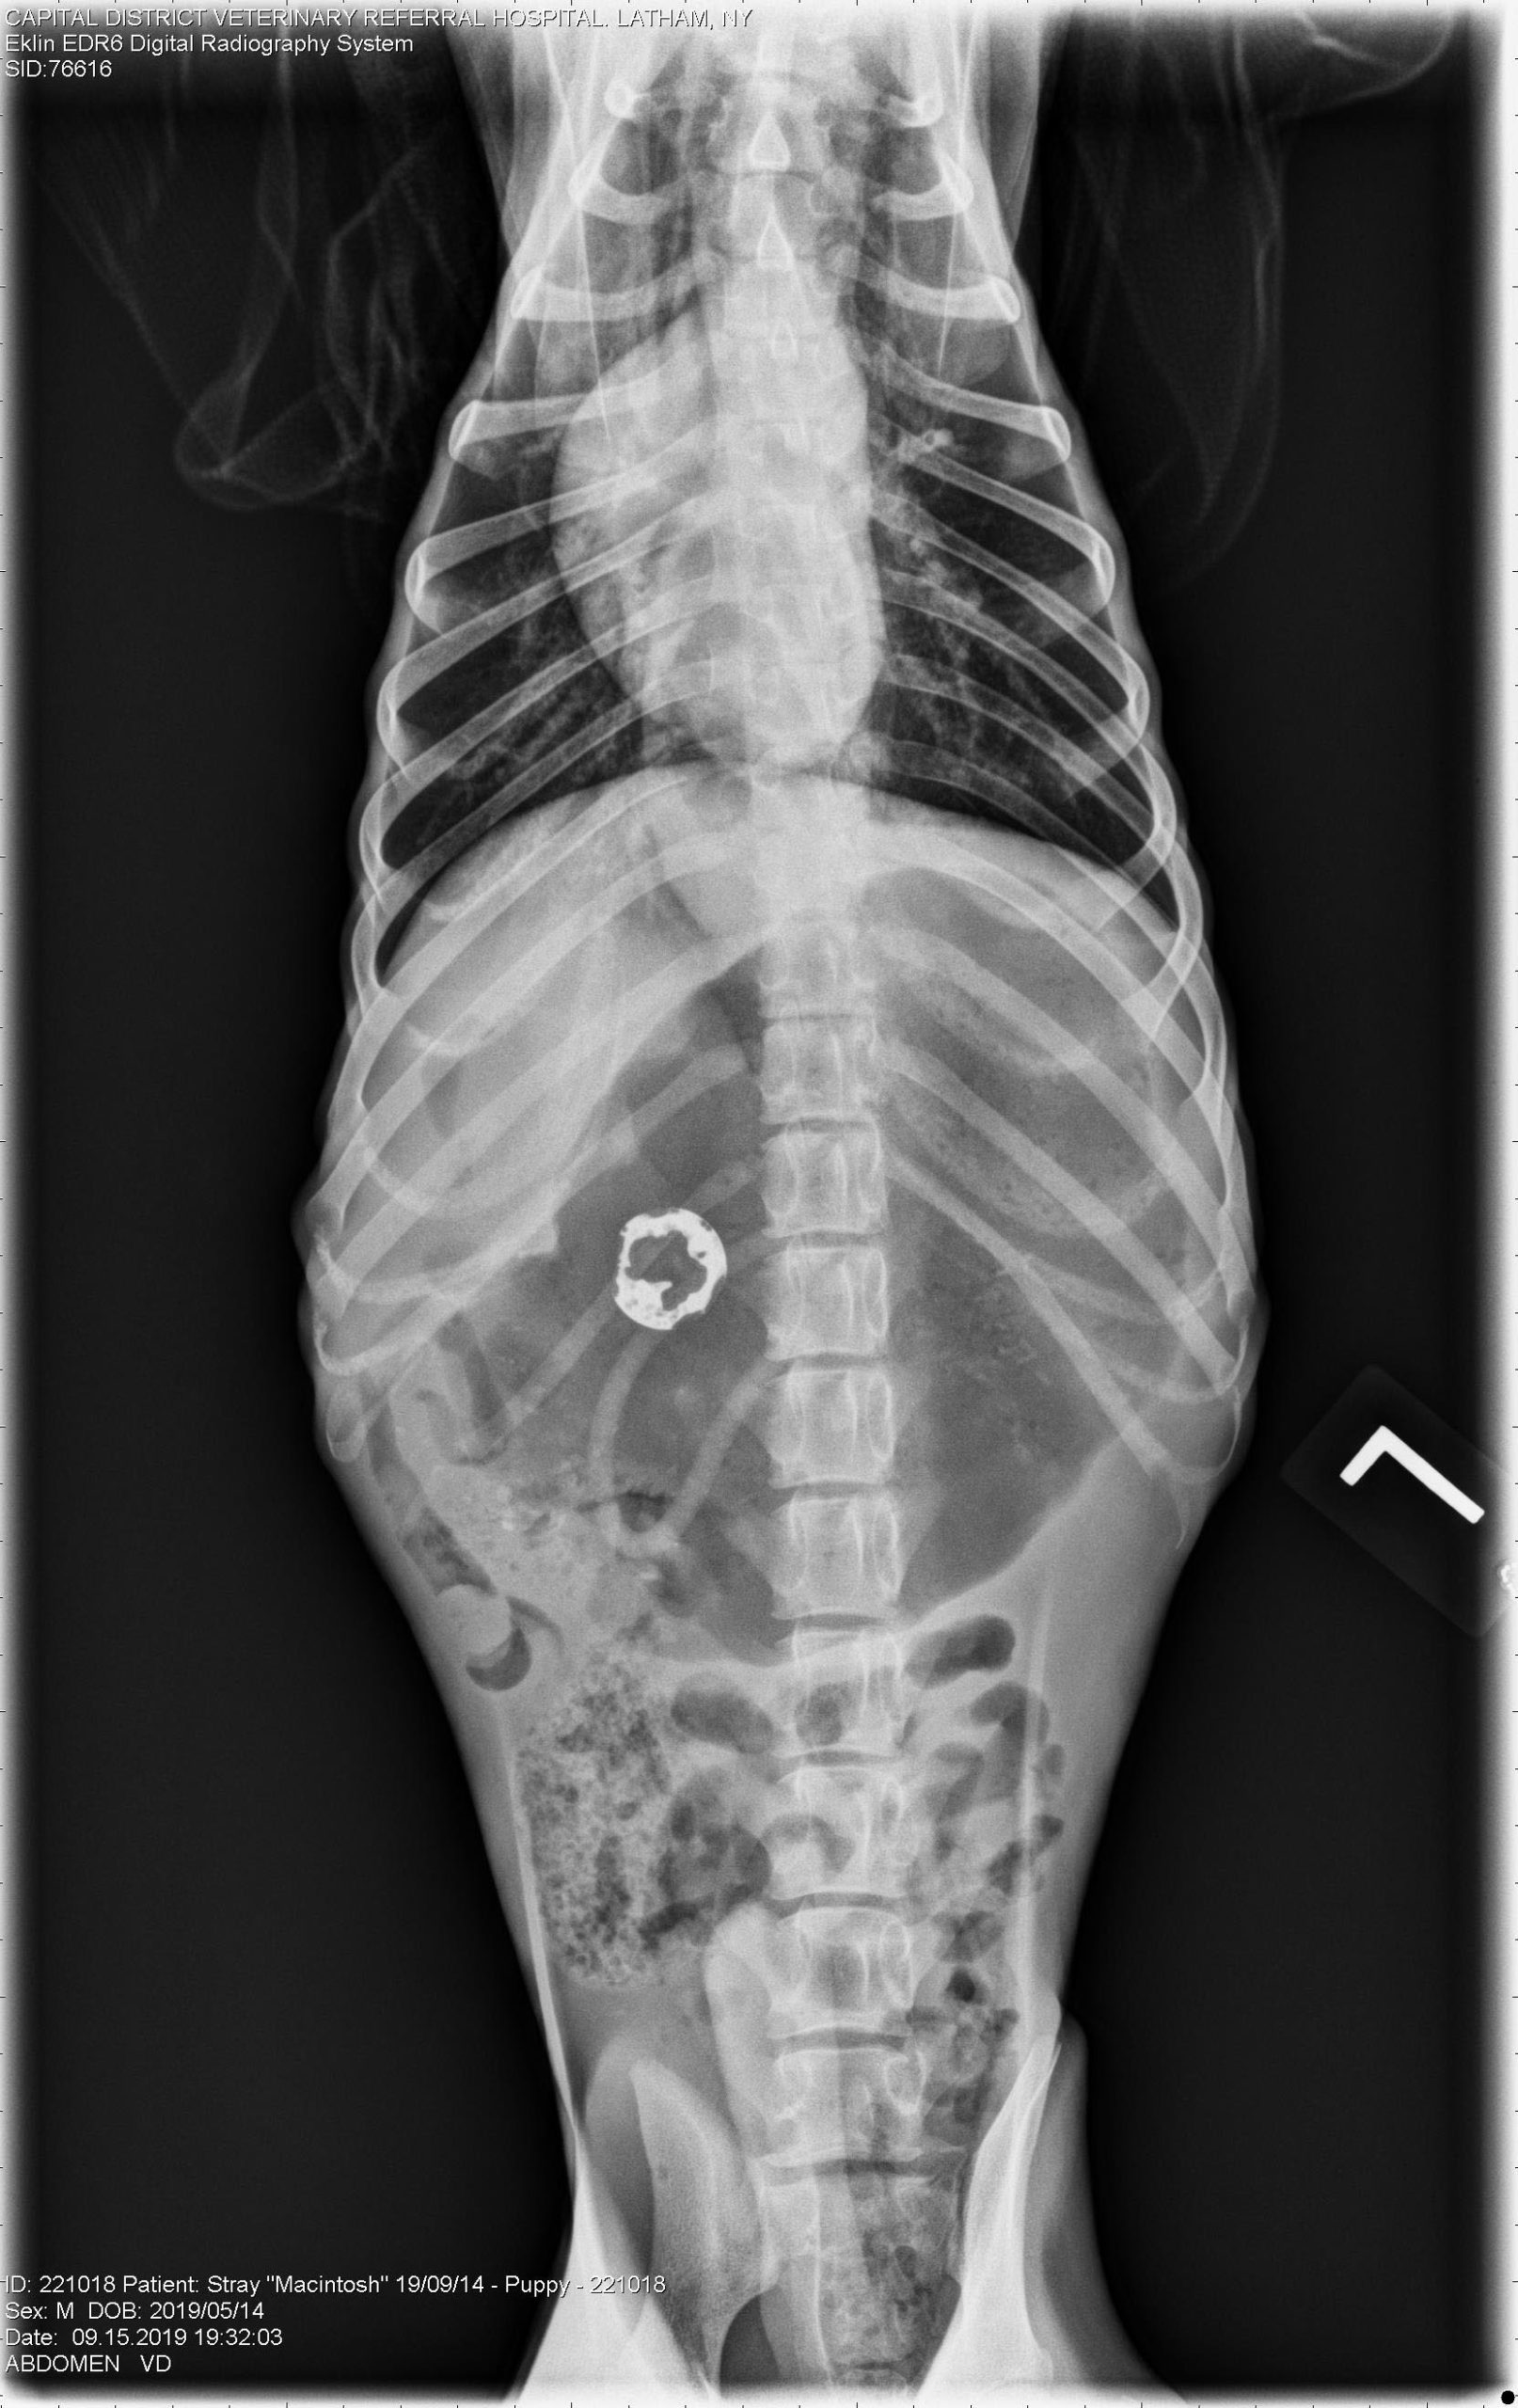

Zinc Toxicosis Dogs . Icterus (yellow mucous membranes) liver failure; Zinc is an essential trace element required for the normal functioning of many enzyme systems, but ingestion of zinc foreign bodies (e.g. The clinical signs of zinc toxicosis include: Ingestion of metal objects containing zinc or high dietary levels of zinc cause the more classic clinical signs of zinc toxicosis (eg, intravascular. Abdominal radiography and a thorough patient history (including vomiting of. When canines ingest certain types of zinc, there is a formation of toxic zinc. Such objects are typically radiodense. Acute zinc poisoning is a relatively common source of poisoning in dogs. Zinc toxicosis is uncommon but should be considered in dogs with anemia and lethargy, especially with concurrent gi signs.

Ingestion of metal objects containing zinc or high dietary levels of zinc cause the more classic clinical signs of zinc toxicosis (eg, intravascular. Zinc toxicosis is uncommon but should be considered in dogs with anemia and lethargy, especially with concurrent gi signs. Zinc is an essential trace element required for the normal functioning of many enzyme systems, but ingestion of zinc foreign bodies (e.g. The clinical signs of zinc toxicosis include: When canines ingest certain types of zinc, there is a formation of toxic zinc. Icterus (yellow mucous membranes) liver failure; Abdominal radiography and a thorough patient history (including vomiting of. Such objects are typically radiodense. Acute zinc poisoning is a relatively common source of poisoning in dogs.

Zinc Toxicosis Dogs Zinc is an essential trace element required for the normal functioning of many enzyme systems, but ingestion of zinc foreign bodies (e.g. Abdominal radiography and a thorough patient history (including vomiting of. When canines ingest certain types of zinc, there is a formation of toxic zinc. Zinc toxicosis is uncommon but should be considered in dogs with anemia and lethargy, especially with concurrent gi signs. Such objects are typically radiodense. Acute zinc poisoning is a relatively common source of poisoning in dogs. Icterus (yellow mucous membranes) liver failure; Ingestion of metal objects containing zinc or high dietary levels of zinc cause the more classic clinical signs of zinc toxicosis (eg, intravascular. The clinical signs of zinc toxicosis include: Zinc is an essential trace element required for the normal functioning of many enzyme systems, but ingestion of zinc foreign bodies (e.g.